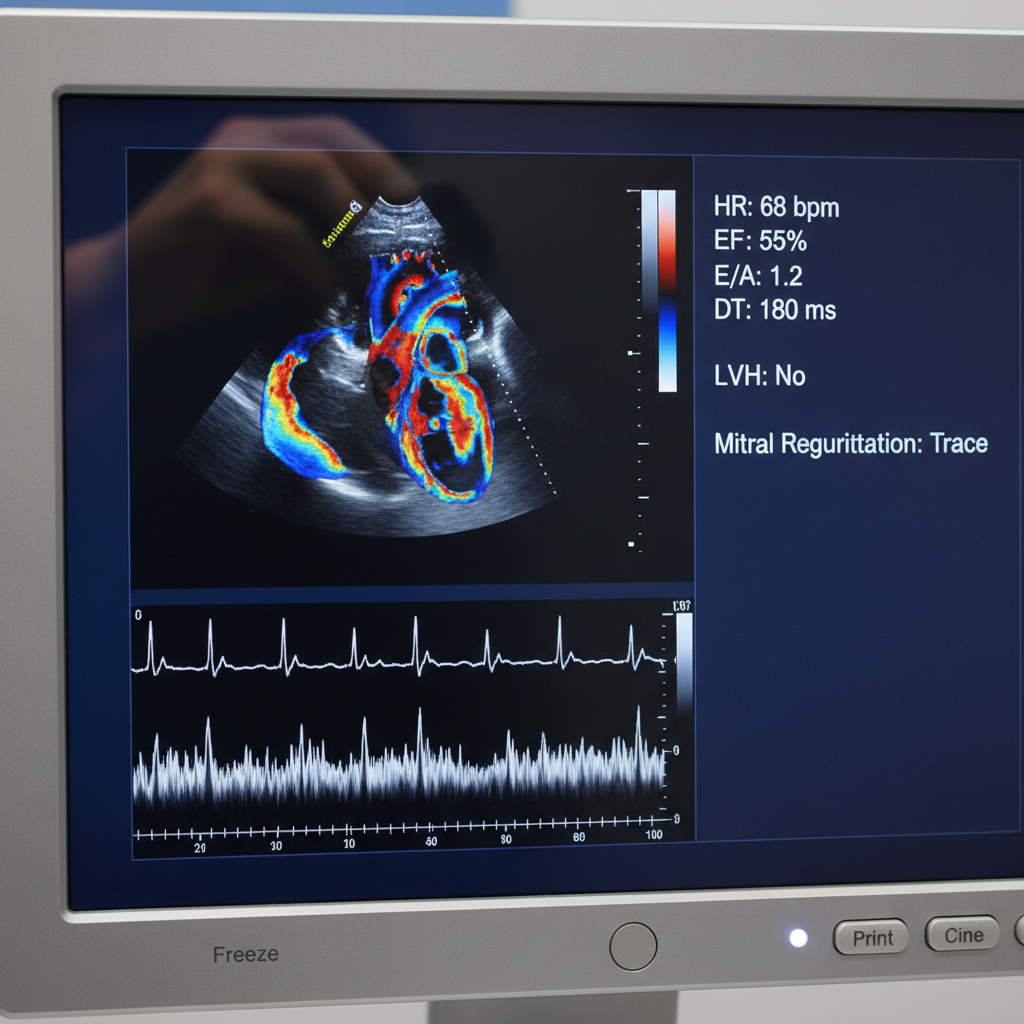

- Siêu âm tim Doppler: Sử dụng hiệu ứng Doppler để đo tốc độ và hướng của dòng máu trong tim.

- Hình dáng, kích thước, và khả năng co bóp của tim: Đánh giá sức khỏe của từng buồng tim.

- Chức năng van tim: Phát hiện bệnh lý hở hoặc hẹp van tim.

- Sức bơm máu của tim: Đo phân suất tống máu để xác định hiệu quả của tim.